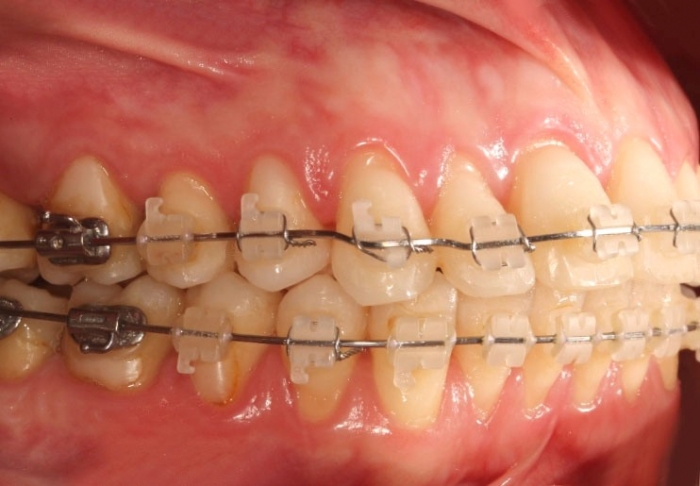

Oclusão após a cirurgia